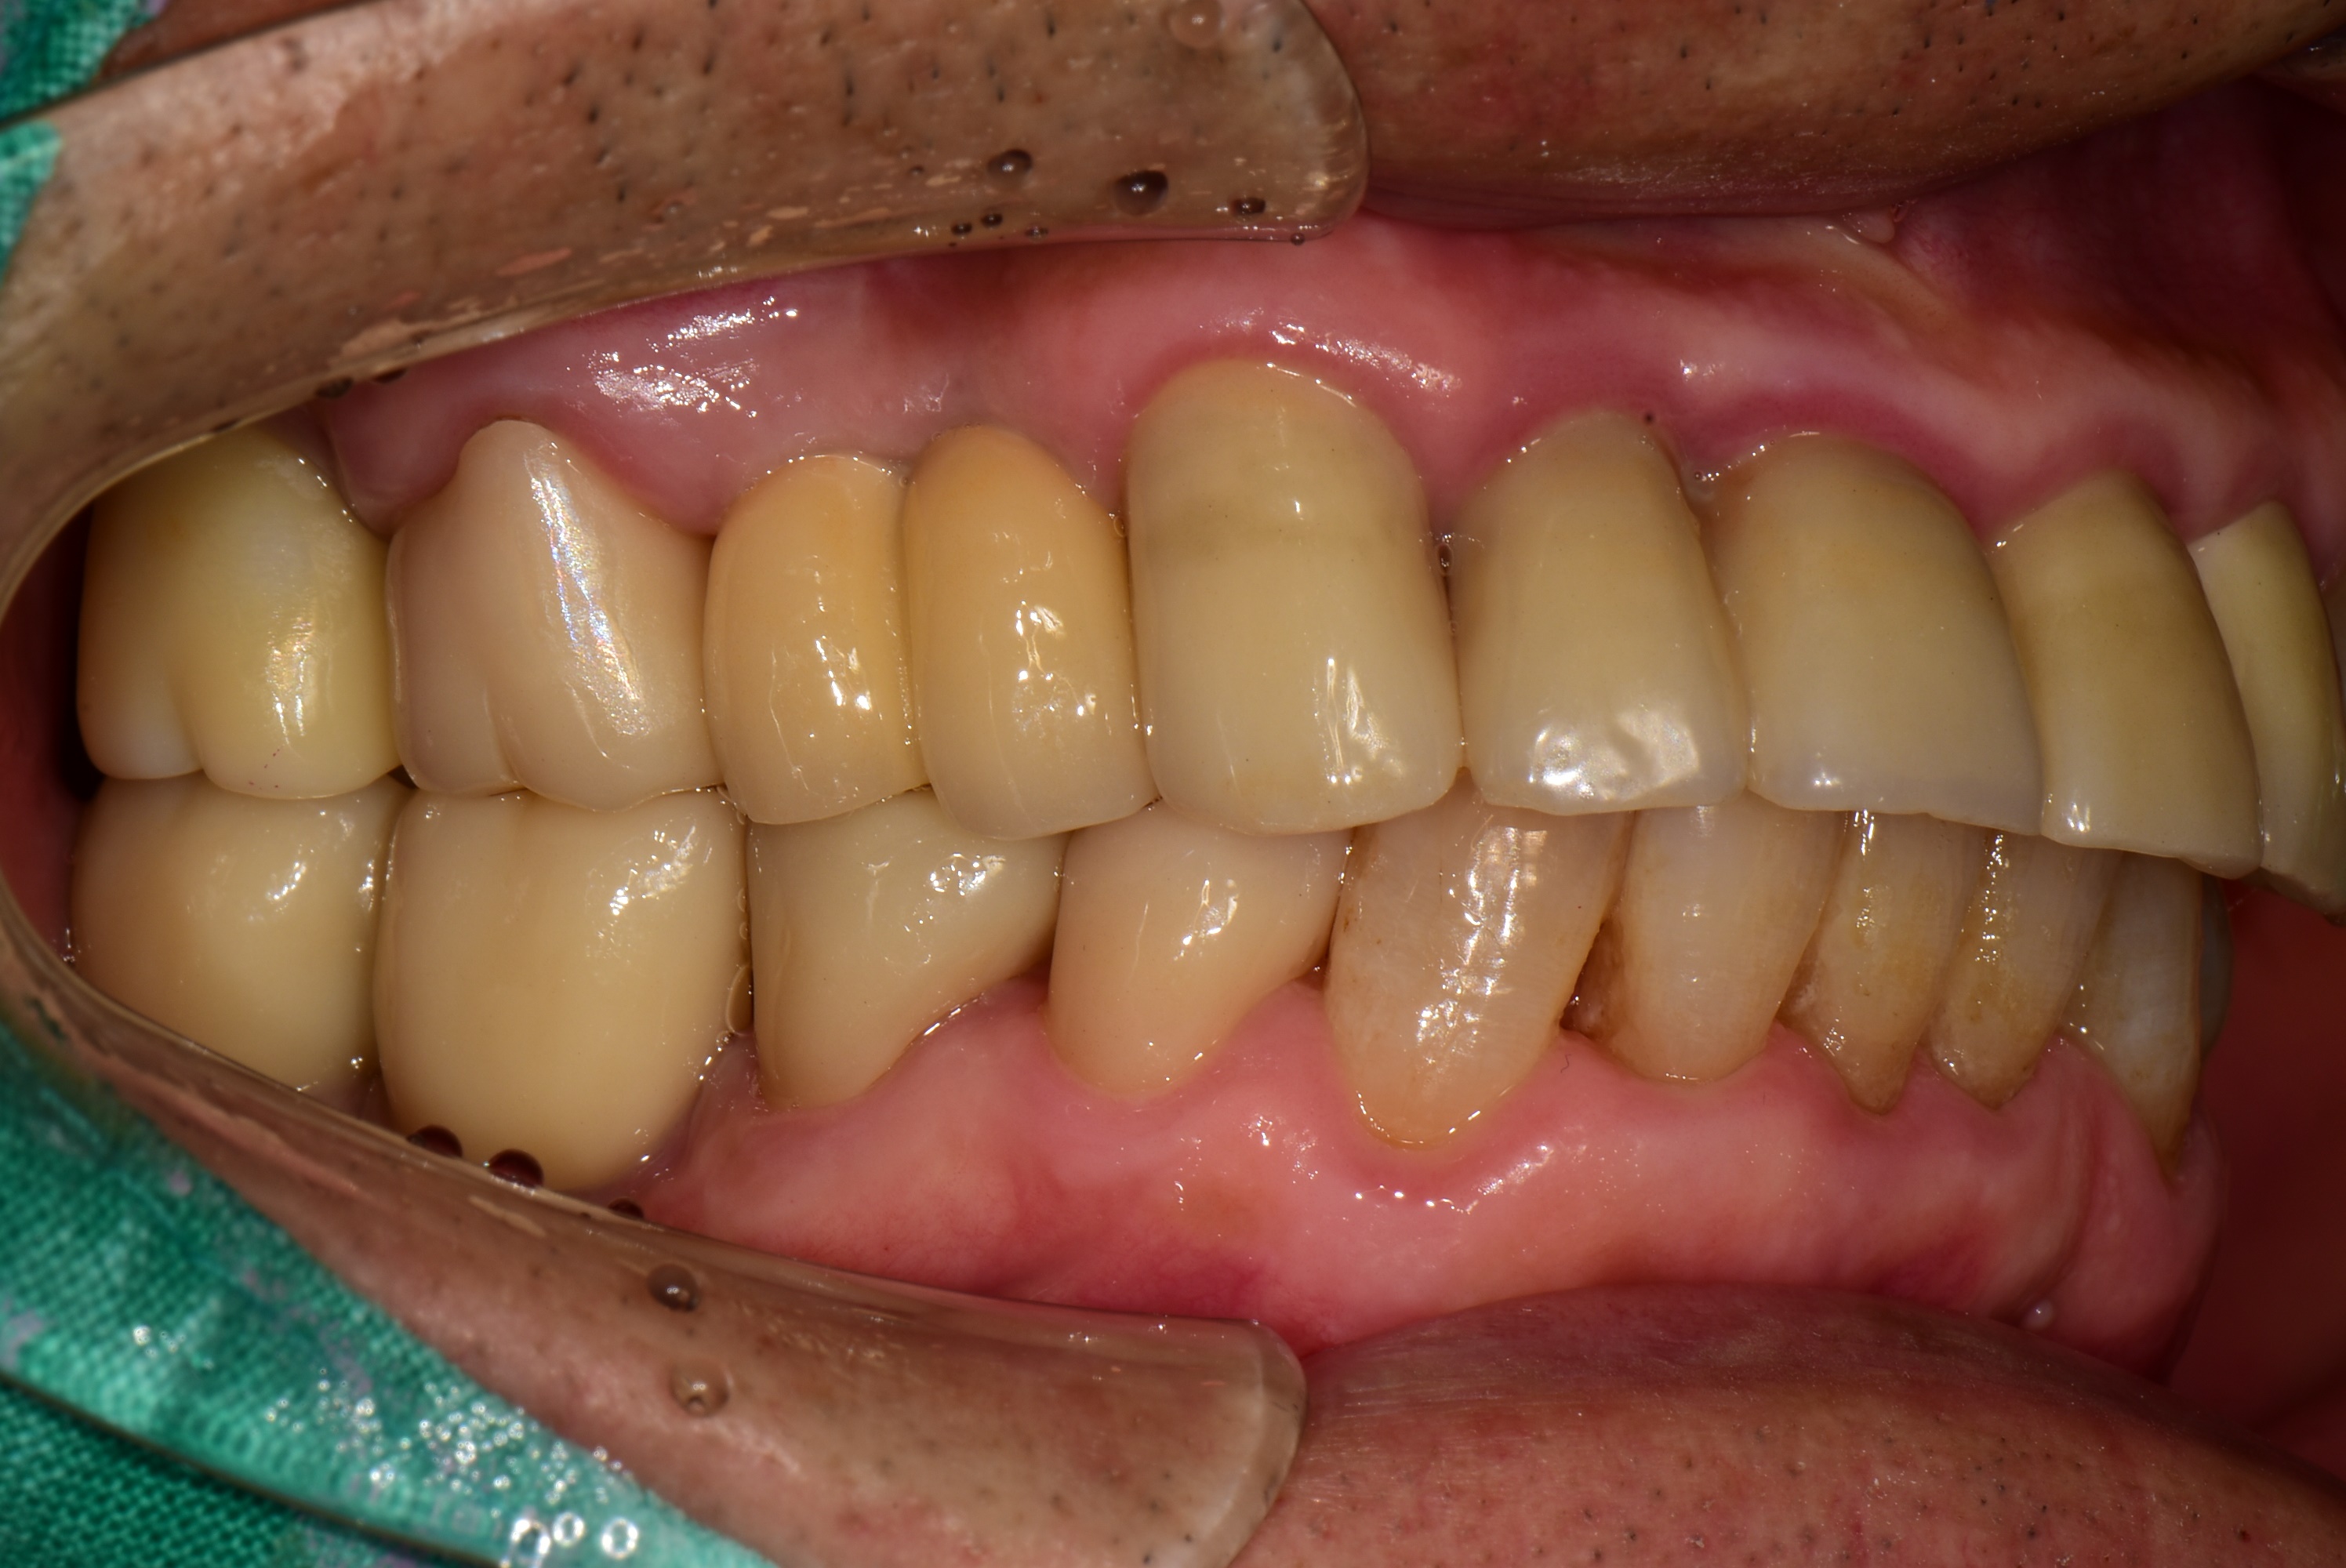

풍무동 서울케이치과에 처음 내원시 충치가 심해서 뿌리만 남은 어금니가 대부분인 상태여서, 식사가 어려웠던 분이었습니다.

어금니 부위 10개 임플란트, 앞니 2개 임플란트를 식립하여 전체 치아를 재건해드린 사례입니다.

<치료 전>